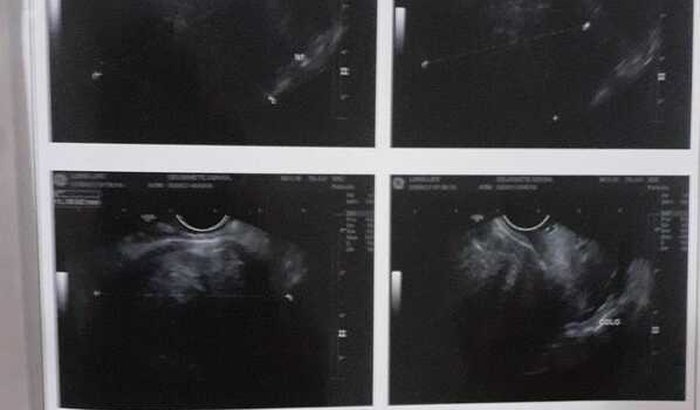

Ola irmãos a paz do Senhor. Meu nome é Deurinete sou moradora do itapoa DF e estou enfrentando um problema muito grave. EStout com alguns miomas que cada vez mais cresce, e por causa desses miomas o meu útero está com o tamanho bem aumentado. Estou correndo risco de vida, a médica que está cuidando doeu caso me disse que preciso fazer essa cirurgia da retirada do útero com muita urgência , pois se eu não fizer posso morrer. Tenho muita hemorragia, fico muito fraca e agora não consigo mais trabalha. Gostaria de pedir em nome Jesus que me ajudem.